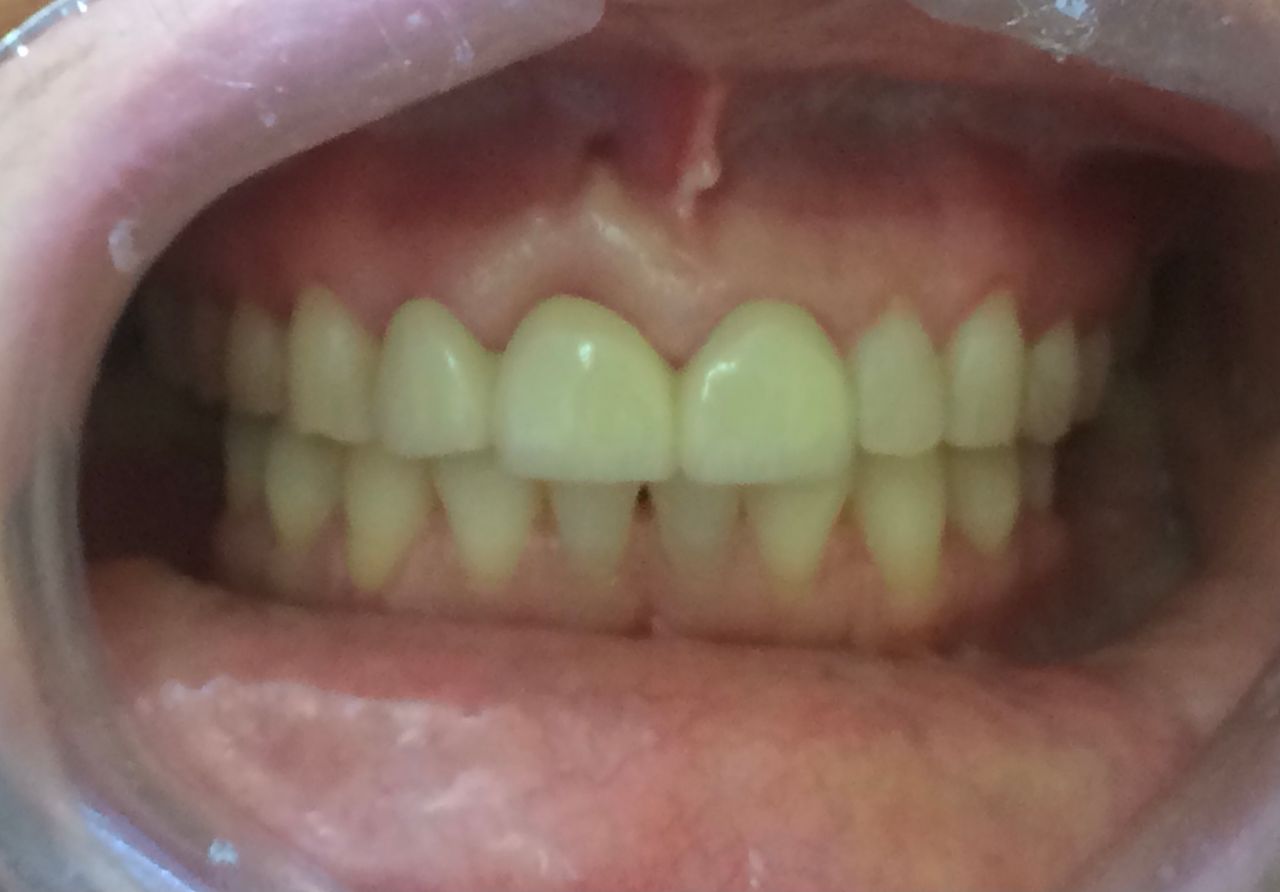

Contamos con odontología digital de vanguardia que nos permite realizar diseños de sonrisa personalizados, tratamientos de alineación dental mediante alineadores como alternativa a la ortodoncia convencional, así como la colocación de coronas y carillas de porcelana, fundamentales para lograr una sonrisa estética, armónica y funcional.

Diseño de sonrisa

Una alternativa inovadora para cambiar la forma y color de dientes es mediante el sistema U Venner de carillas de porcelana o de ceromero. Previamente se requiere de fotografías intraorales, toma de moldes dentales y toma de color dental. Excelente opción para diseñar una nueva sonrisa.